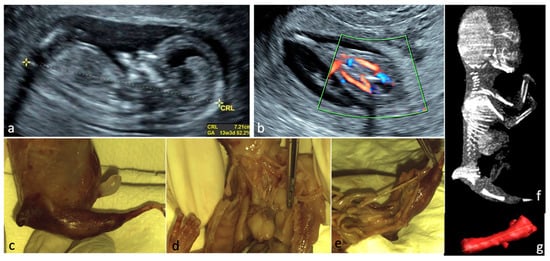

From Diagnosis to Decision—Fetal Limb Abnormalities

by Andreea Florentina Stancioi-Cismaru, Razvan Grigoras Capitanescu, Mihaela-Simona Naidin, Cristian Constantin, Marina Dinu, Florin Burada, Oana Sorina Tica, Mihaela Gheonea, Bianca Catalina Andreiana, Razvan Cosmin Pana and Stefania Tudorache

J. Clin. Med. 2026, 15(2), 486; https://doi.org/10.3390/jcm15020486 - 8 Jan 2026

Background/Objectives: Our aim was to investigate the diagnostic accuracy of prenatal ultrasound (US) in fetal limb abnormalities. As a secondary target, we wanted to correlate various predictors for the diagnosis accuracy. Methods: We prospectively enrolled cases with routine prenatal US performed in five [...] Read more.

Background/Objectives: Our aim was to investigate the diagnostic accuracy of prenatal ultrasound (US) in fetal limb abnormalities. As a secondary target, we wanted to correlate various predictors for the diagnosis accuracy. Methods: We prospectively enrolled cases with routine prenatal US performed in five participating centers. Subsequently, we selected and processed all cases with limb abnormalities: suspected, diagnosed, and missed on the prenatal diagnosis scans. We collected data on the type of anomaly, the US equipment and probes used, the operator’s expertise, the gestational age at the diagnosis, the length of the examination, and the use of US reporting form. SPSS 22.0 software was applied to perform the analyses using non-parametric statistical methods. Associations between categorical variables were evaluated using Fisher’s exact test and Chi-square tests. For correlations between the gestational age and the anomaly severity, we used Spearman’s rank-order correlation. Predictive performance of operator- and scan-related variables for diagnostic accuracy was assessed using receiver operating characteristic (ROC) curve analysis, with area under the curve (AUC) estimates, standard errors (SE), confidence intervals (95% CI), and p-values reported. Results: Our data showed that most US examinations were performed as part of routine screening (79.7%), and the most frequent anomaly diagnosed was clubfoot. Operators’ expertise demonstrated the highest predictive performance, while technical parameters—scan duration (AUC = 0.20, p = 0.1188) and US equipment (AUC = 0.30, p = 0.3478)—did not significantly predict diagnostic accuracy. Conclusions: The overall diagnostic accuracy of prenatal US was 85.5%. Our findings indicate that diagnostic performance is driven primarily by operator expertise and training, rather than by gestational age at scan and technical parameters. Full article

Show Figures

Figure 1